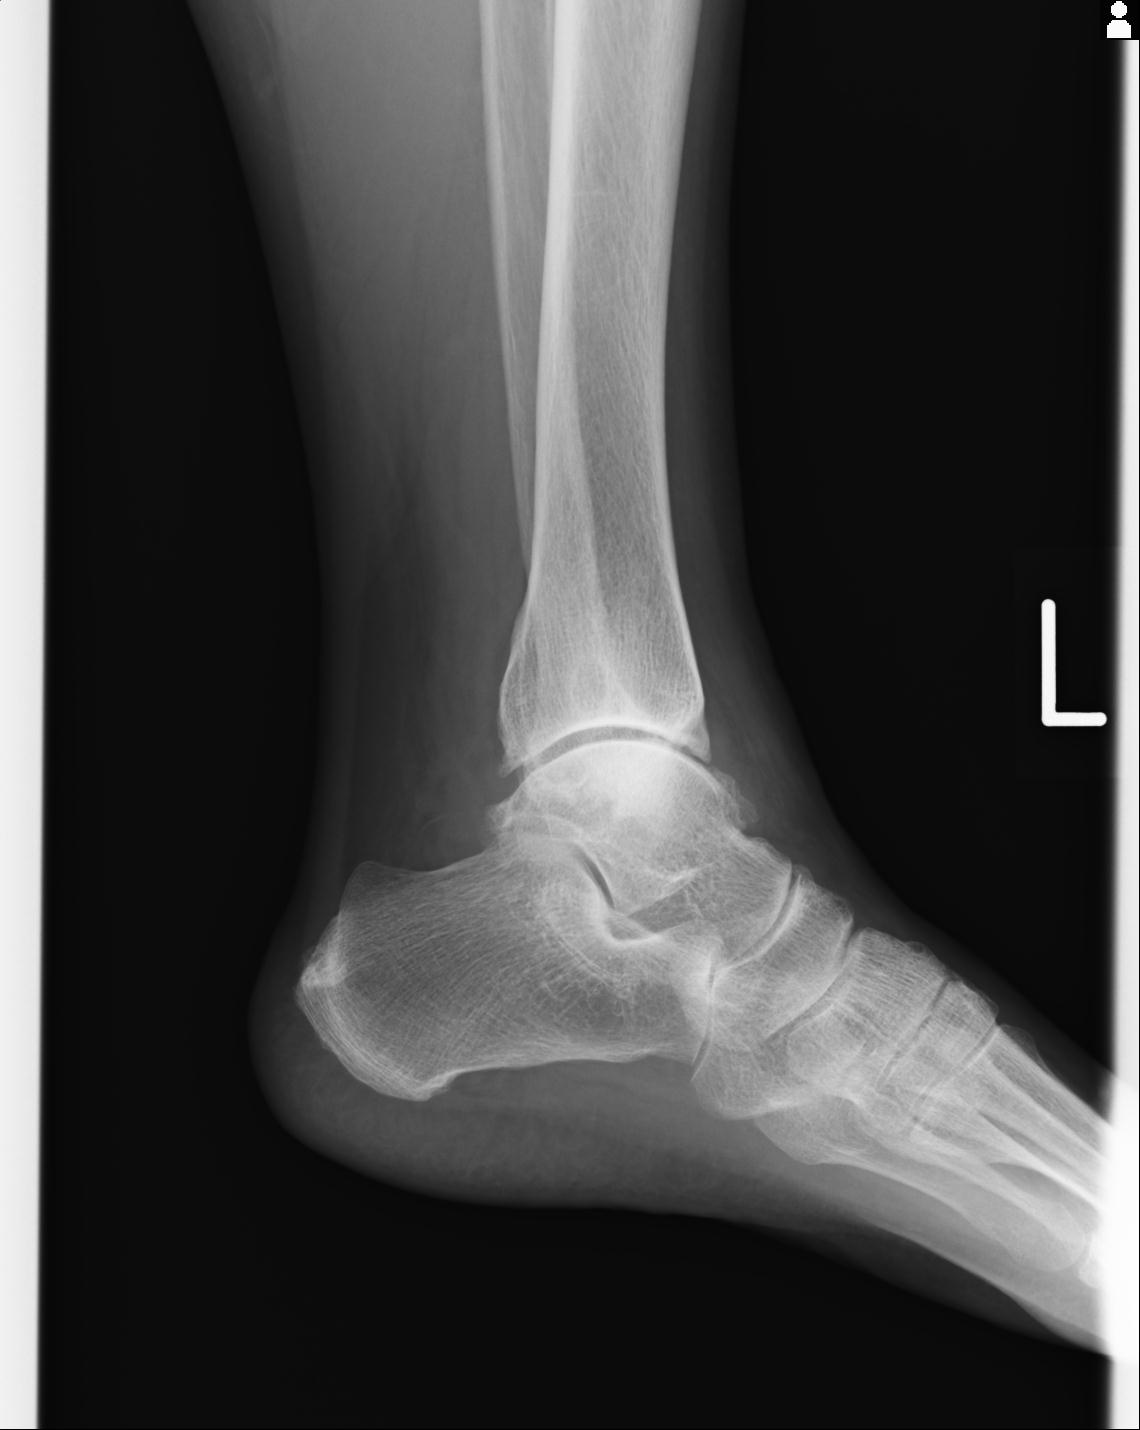

56476 8/28 4R 1/21 2R 左足関節 デジカメ写真 72歳女性 右足関節AS